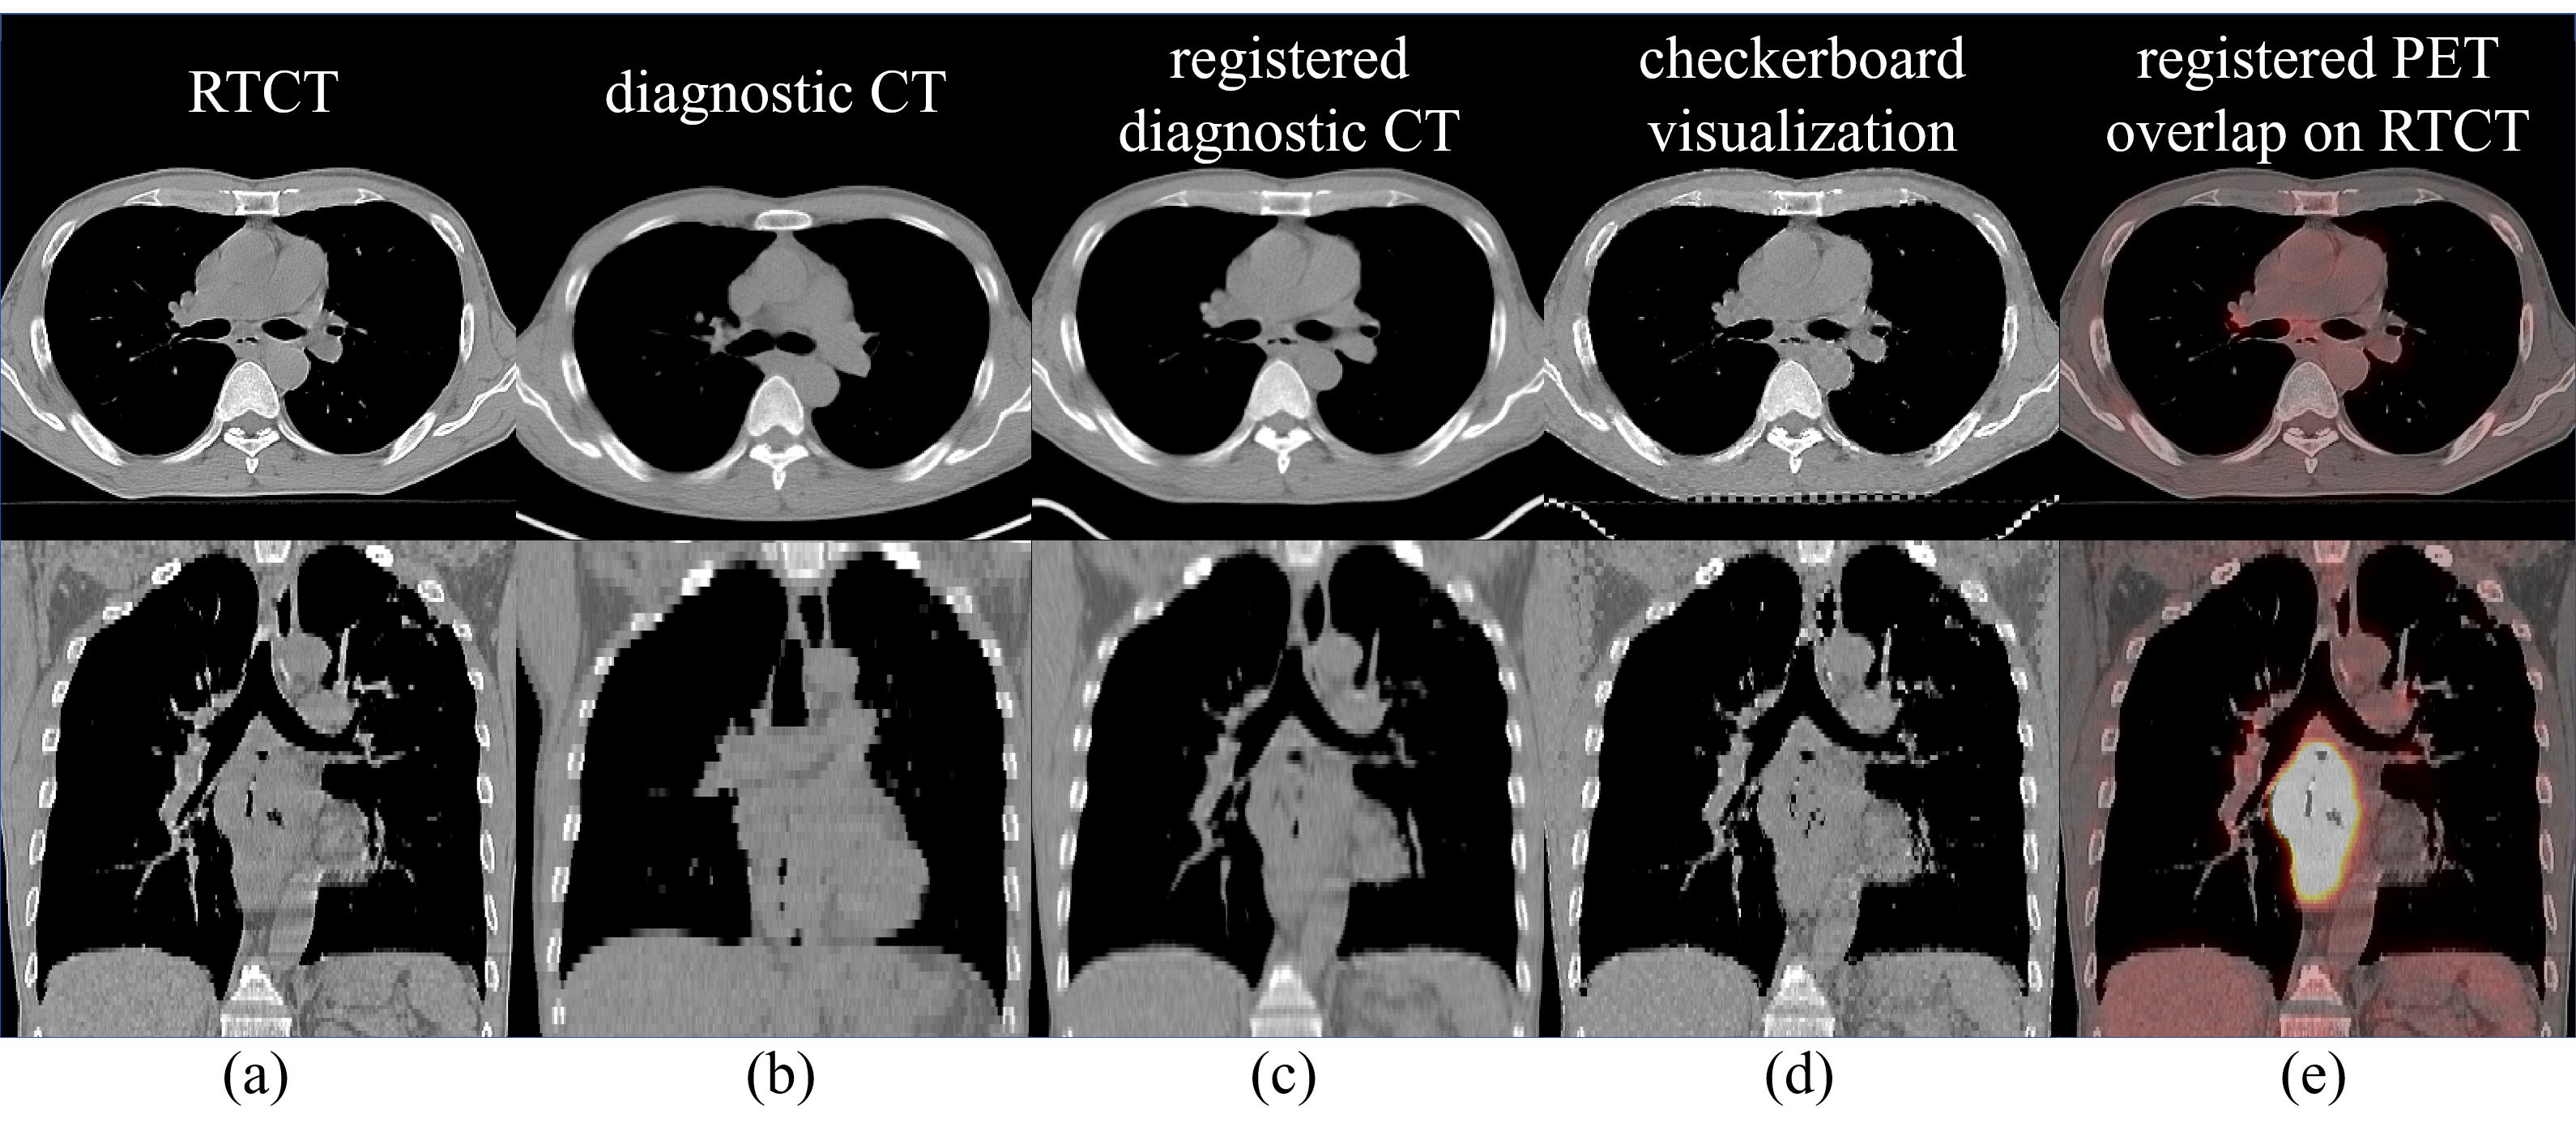

To generate aligned \acPET/\acRTCT pairs, we register the former to the latter. This is made possible by the diagnostic \acCT accompanying the \acPET. To do this, we apply the cubic B-spline based deformable registration algorithm in a coarse to fine multi-scale deformation process [13]. We choose this option due to its good capacity for shape modeling and efficiency in capturing local non-rigid motions. However, to perform well, the registration algorithm must have a robust rigid initialization to manage patient pose and respiratory differences in the two CT scans. To accomplish this, we use the lung mass centers from the two \acCT scans as the initial matching positions. We compute mass centers from masks produced by the P-HNN model [3], which can robustly segment the lung field even in severely pathological cases. This leads to a reliable initial matching for the chest and upper abdominal regions, helping the success of the registration. The resulting deformation field is then applied to the diagnostic \acPET to align it to the \acRTCT at the planning stage. One registration example is illustrated in Fig. 3.

Refer to caption

Figure 3: Deformable registration results for a patient shown in axial and coronal views. (a) shows the RTCT image; (b, c) depicts the diagnostic CT image before and after the registration, respectively; (d) depicts a checkerboard visualization of the RTCT and registered diagnostic CT images; and (e) overlays the PET image, transformed using the diagnostic CT deformation field, on top of the RTCT.